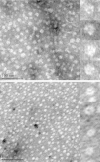

Glycolysis is essential to Trypanosoma brucei, the causative agent of African sleeping sickness, suggesting enzymes in the pathway could be targets for drug development. Ebselen (2-phenyl-1,2-benzisoselenazol-3(2H)-one, EbSe) was identified in a screen as a potent inhibitor of T. brucei hexokinase 1 (TbHK1), the first enzyme in the pathway. EbSe has a history of promiscuity as an enzyme inhibitor, inactivating proteins through seleno-sulfide conjugation with Cys residues. Indeed, dilution of TbHK1 and inhibitor following incubation did not temper inhibition suggesting conjugate formation. Using mass spectrometry to analyze EbSe-based modifications revealed that two Cys residues (C327 and C369) were oxidized after treatment. Site-directed mutagenesis of C327 led to enzyme inactivation indicating that C327 was essential for catalysis. C369 was not essential, suggesting that EbSe inhibition of TbHK1 was the consequence of modification of C327 via thiol oxidation. Additionally, neither EbSe treatment nor mutation of the nine TbHK1 Cys residues appreciably altered enzyme quaternary structure.